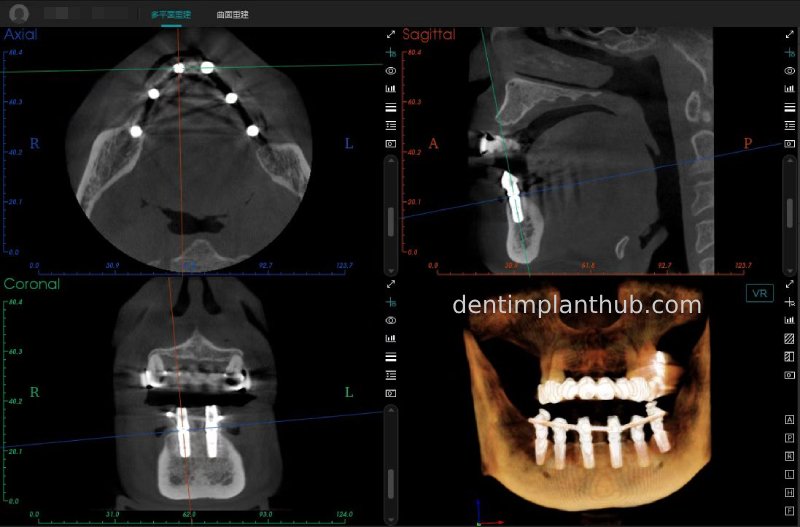

A review of the CBCT on 6/10/23 was more promising and a surgical plan was subsequently drawn up.

CBCT review results on 13 May '24

46

44

42

32

34

36